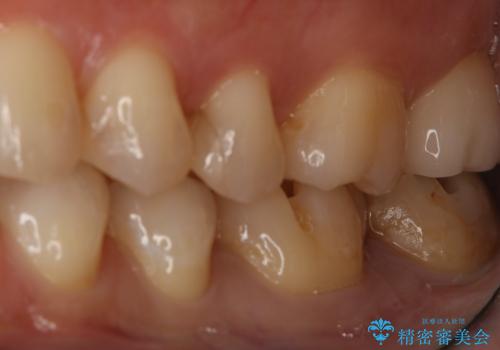

- 左下6、7番の虫歯をセラミックにて治療を希望された患者様です。

切削量を考慮してセラミックインレーを選択しました。

7番は虫歯が深かったのでCR裏層した上で形成、印象をしています。